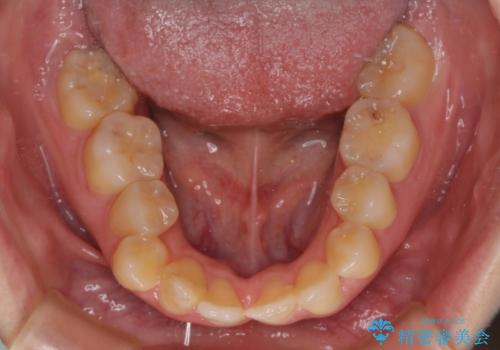

後戻りの再矯正 ワイヤー装置でデコボコと隙間を改善

- 学生時代の抜歯矯正の後戻りが気になり、再矯正を希望して来院された患者様です。

詰め物で隠していた下顎前歯の隙間は、歯軸を改善することで詰め物を除去しても隙間が目立たなくなりました。

まだ改善したいところはありましたが、患者様自身は大変満足されたとのことで、治療を終えることとなりました。